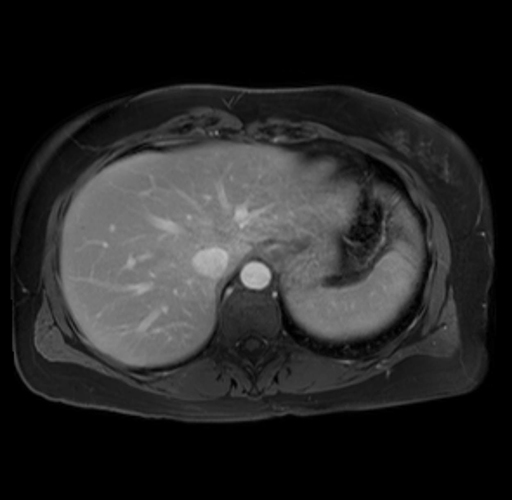

Imaging Analysis

Look through the patient's CT scan to identify any areas of concern for the necessary procedure.

Based on your CT findings, which issue(s) are present and would give reason for "planned slowing down moment(s)" in this case?

Considering a standard distal pancreatectomy procedure, what step(s) of the operation would you do differently in this case?